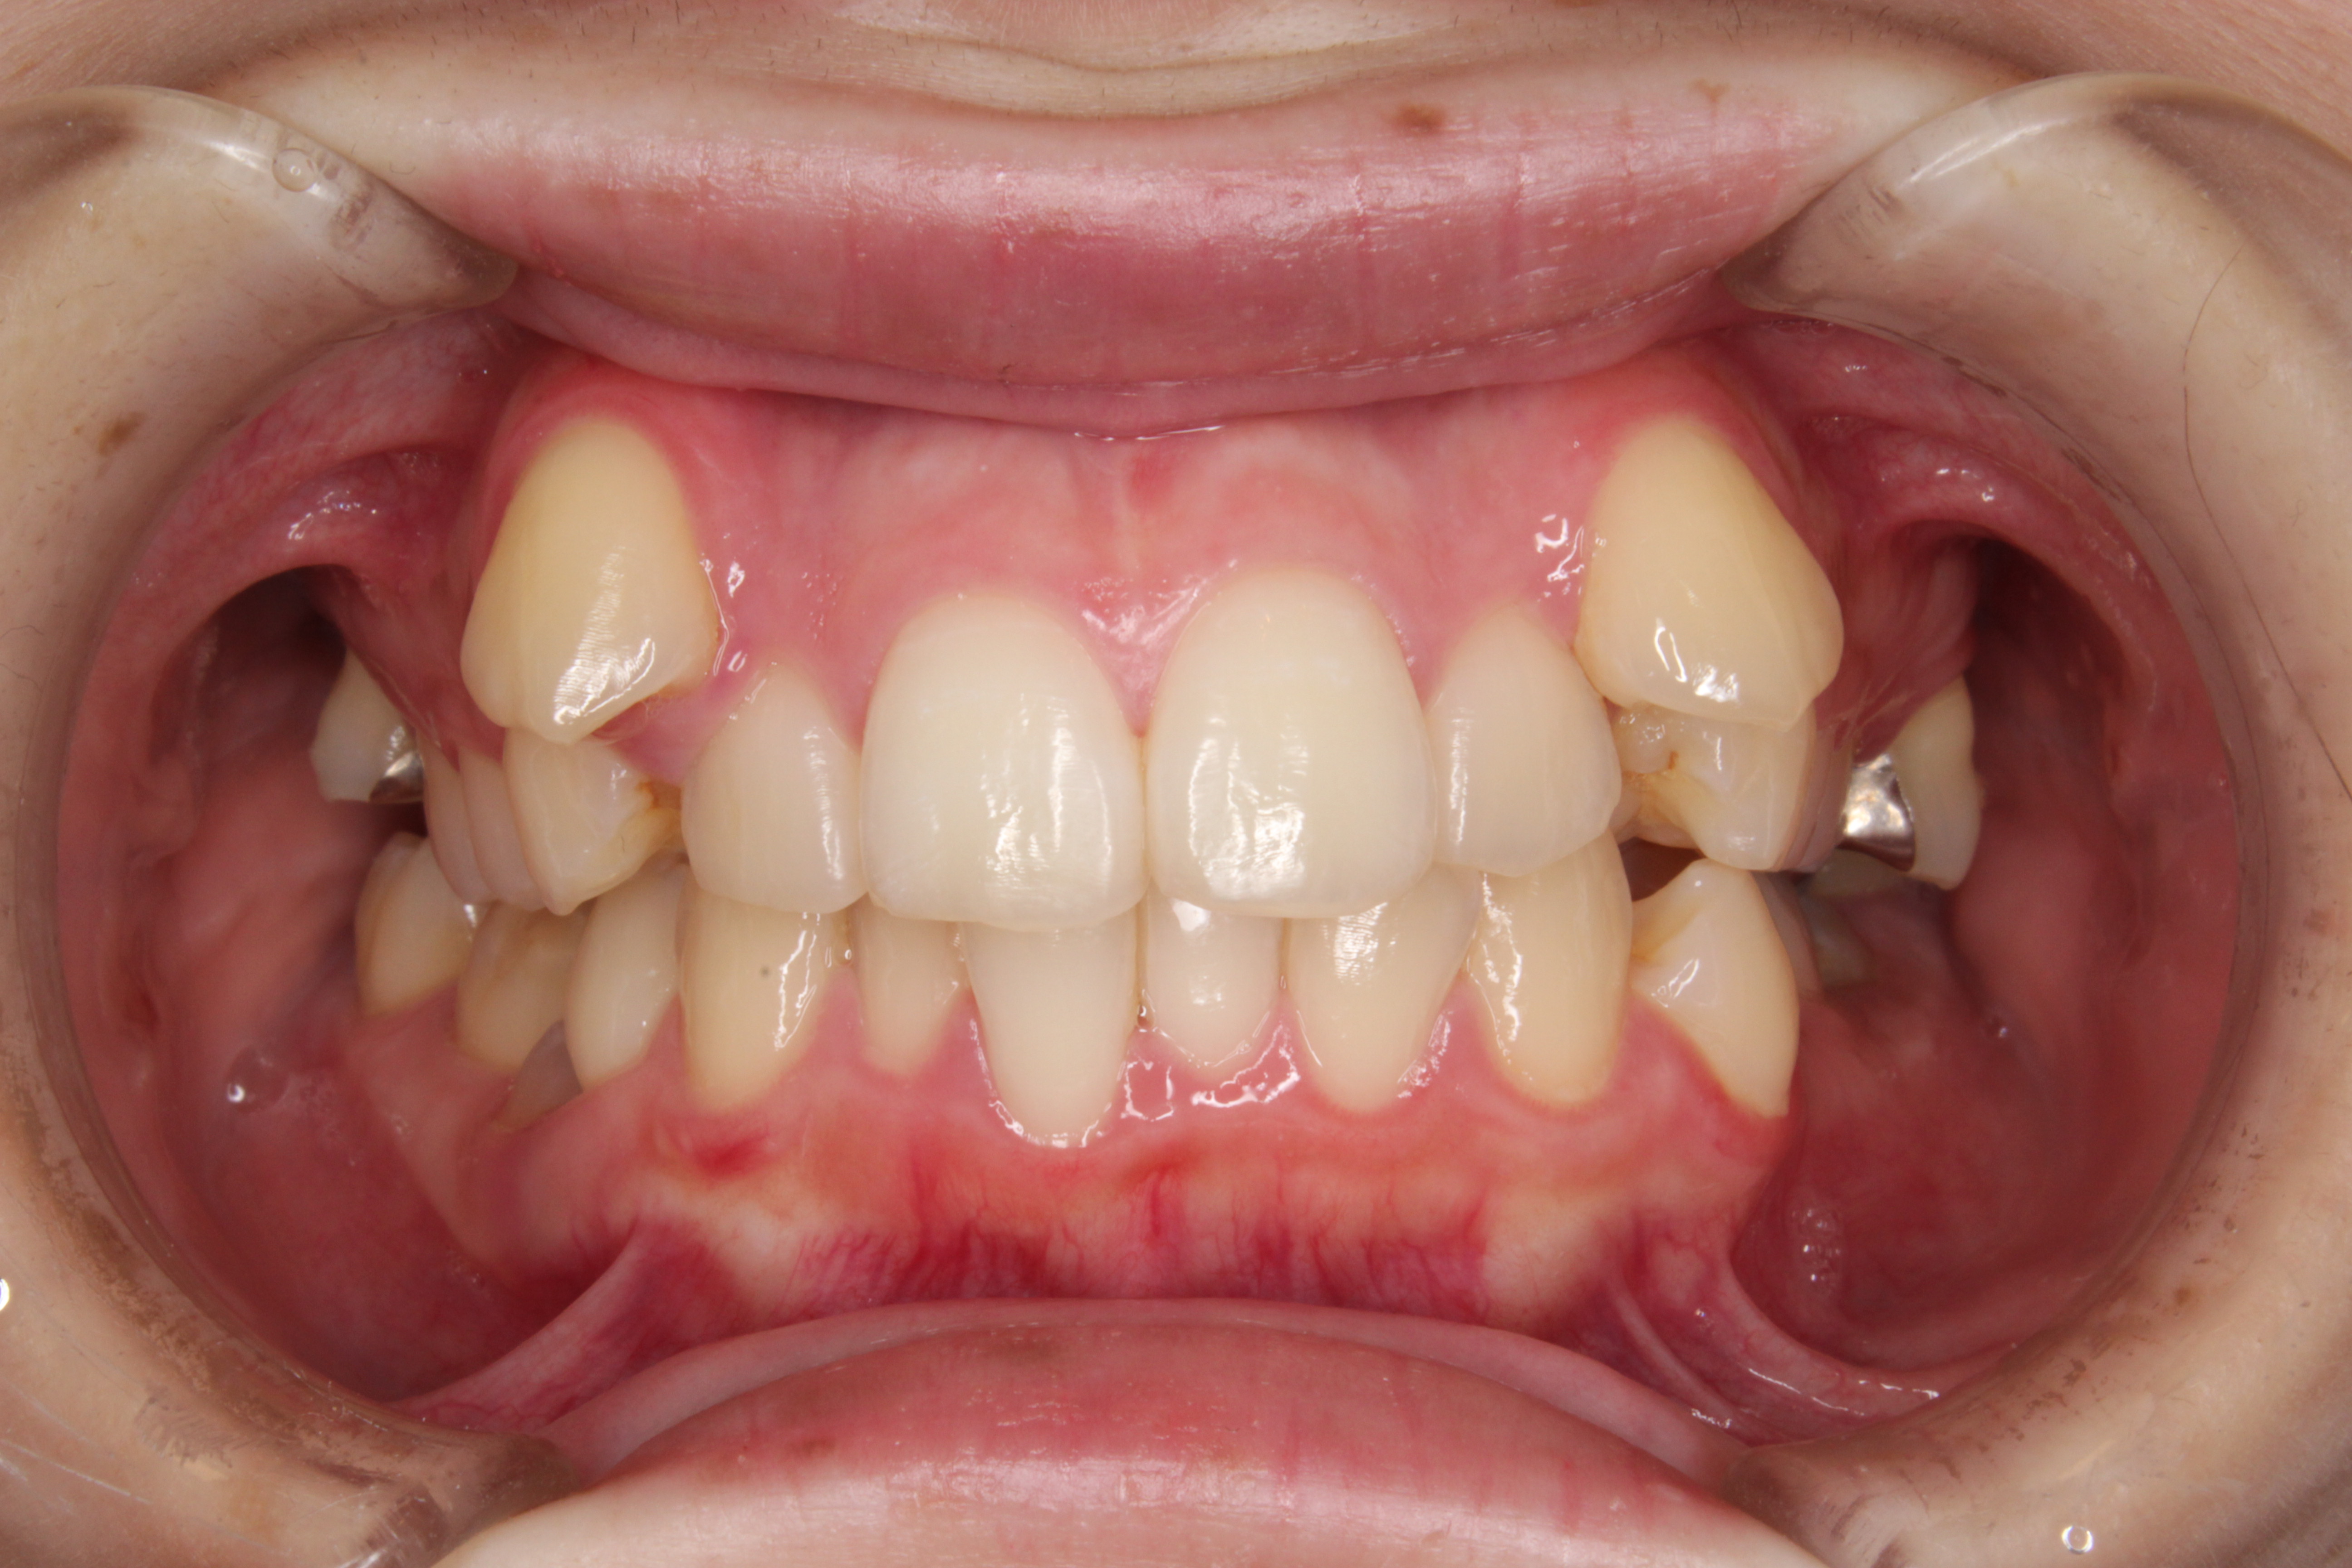

歯のデコボコを治したい

年齢層 20代

性別 女性

主訴 【主訴】歯のデコボコを治したい 【診断・症状】上下凸凹

治療費用 検査・診断:38,500-/裏側矯正治療:1,397,000-(※全て税込)

治療期間 約3年半(45回)

抜歯 有(上4,4、下 4,4)

矯正の装置 裏側矯正(舌側矯正)

副作用、リスク 歯肉退縮,歯根吸収,疼痛,咬合の違和感,装置の違和感,虫歯,歯肉炎

case7_デコボコ抜歯_before

Before